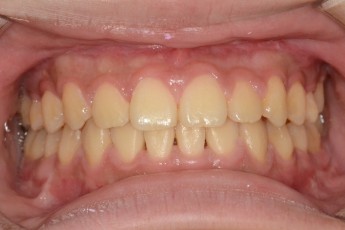

BEFORE & AFTER

- 덧니교정